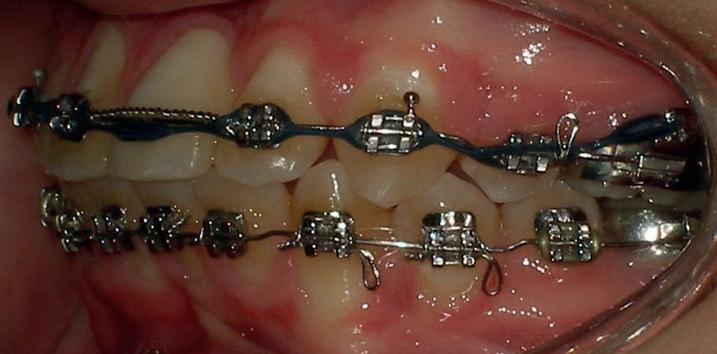

RECONFIGURAREA suportului osos implantar. În cazul prezentat, după ani de terapie ortodontică incorect executată, dezvoltarea dentară a pacientului a complicat obținerea unui zâmbet estetic. S-a reanalizat și s-a optat pentru abordare interdisciplinară care cuprinde chirurgia parodontală, un al doilea tratament

ortodontic și protetica pentru a oferi îngrijirea comprehensivă.